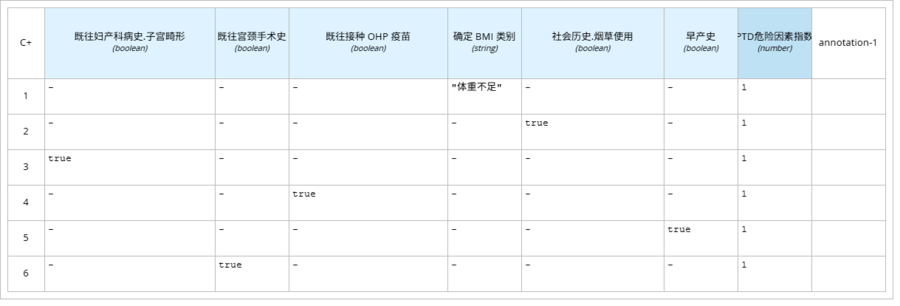

l “PTD危险因素指数”即创伤后应激障碍危险因素指数“早产史”、“确定BMI类别”、“既往接种OHP疫苗”、“既往宫颈手术史”、“社会历史”、“既往妇产科病史”进行统计,使用决策表。